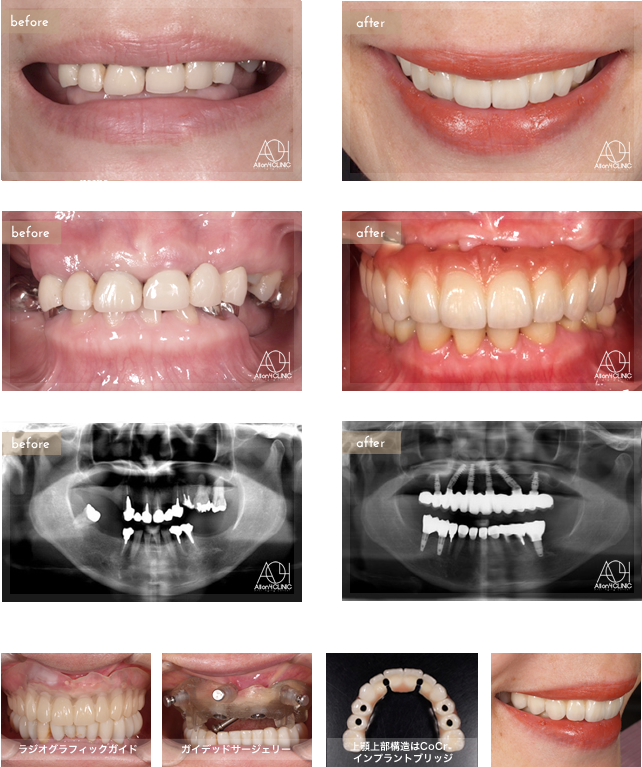

Age : 61

Sex : Female

Treatment :

- Maxilla All-on-4

- Under All-on-4

上顎はNobel Active6本、左右サイナスフロアエレベーション。上顎上部構造はCoCrインプラントブリッジ(Core3DCentres) (歯肉:セラミック 歯:セラミック)